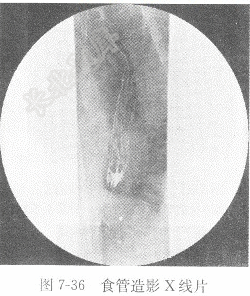

试题详情单项选择题男性,71岁,呕血1次,治疗后复查,食管造影图像见图7-36,X线诊断为( )。 A、反流性食管炎B、正常食管C、食管静脉曲张D、食管癌正确答案:关注下方微信公众号,搜题查看答案热门试题血清氨基转移酶血清无机磷男性,73岁,痰中带血2周,X线影像见图脑脊液生化动脉血氧饱和度(SaO2)阵发性室性心动过速心电图诊断步骤与报告内容题见图6-5。 二氧化碳结合力(CO2CP)硬膜下血肿题见图6-15。肾癌X线片概述血hCG检测典型浸润型肺结核心房颤动检查肾结石心房颤动心室颤动转移性肝癌